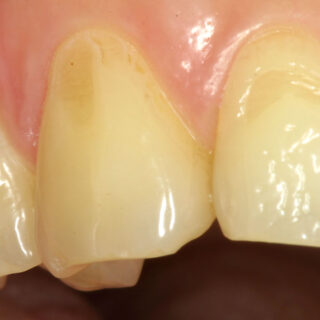

Una fractura dental por debajo de la encía es una de las situaciones más complejas en odontología. Muchos pacientes acuden a consulta pensando que la única solución es extraer el...